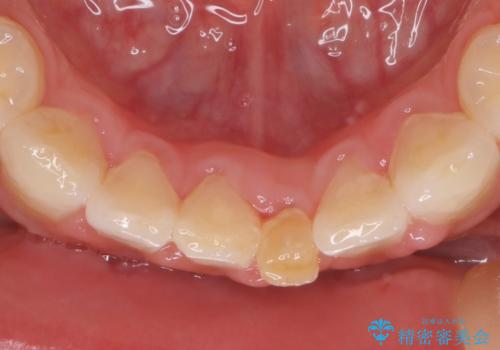

- 晩期残存した下顎乳中切歯の変色を主訴に来院されました。

後続永久歯は先天性欠如しており、下顎前歯のブリッジにて補綴治療を行なっております。